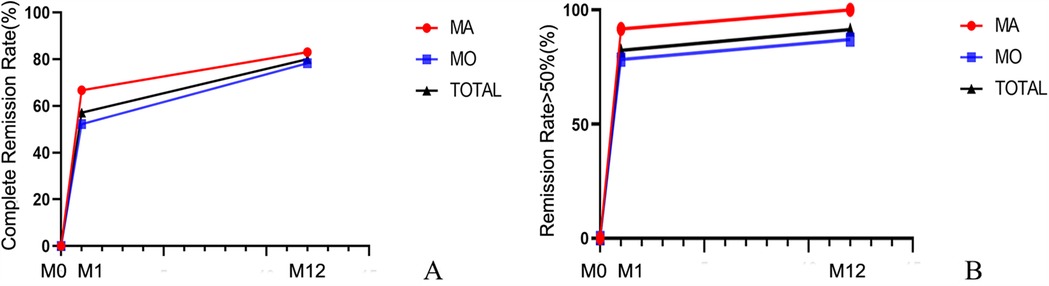

Among the 35 children, 12 (34.3%) had migraine with aura and 23 (65.7%) had migraine without aura. There were no differences between the two groups in terms of sex and age. During the 12-month follow-up, 10 children (83%) in the aura group and 18 children (78.3%) in the non-aura group achieved complete remission of migraine. Additionally, 12 children (100%) in the aura group and 20 children (87%) in the non-aura group experienced a reduction in migraine frequency of >50%. There were no statistically significant differences between the aura and non-aura groups (Figure 5, Table 3).

Figure 5. Changes in the remission rate of migraine with aura and migraine without aura over time. (A) Complete Remission Rate; (B) Remission Rate ≥50%. MA, Migraine with aura; MO, Migraine without aura; TOTAL, the overall patient group. M0, 3 months before the intervention; M1, 1 month after intervention; M12, 12 months after intervention.

Table 3. Remission rates of migraine with aura and migraine without aura at different time points after intervention.

Our study demonstrated significant therapeutic benefits of PFO closure in pediatric migraine patients with moderate-to-large right-to-left shunts. At the 1-month follow-up after intervention, 20 patients (57.1%) achieved complete remission, and 29 (82.9%) experienced a reduction in migraine frequency of >50%. At the 12-month follow-up, 28 patients (80%) achieved complete remission, and 32 (91.4%) experienced a reduction in migraine frequency of >50%. During the 12-month follow-up period, the headache-related scores decreased significantly compared to pre-intervention levels, with statistical significance. Both the aura and non-aura groups demonstrated high response rates (83% vs. 78.3% complete remission; 100% vs. 87% achieving >50% frequency reduction), with no statistically significant intergroup differences (Figure 5, Table 3). The reduction in NRS-11 at 12 months after intervention was more pronounced in the aura group than in the non-aura group (P < 0.05), while there were no statistically significant differences between the two groups in terms of HIT-6, PedMIDAS, and migraine duration. Moreover, no serious adverse events occurred, supporting the safety of the procedure. These findings support the potential therapeutic value of PFO closure in selected pediatric migraine patients, particularly in those demonstrating medication-refractory symptoms coupled with objectively confirmed moderate-to-large right-to-left shunts.